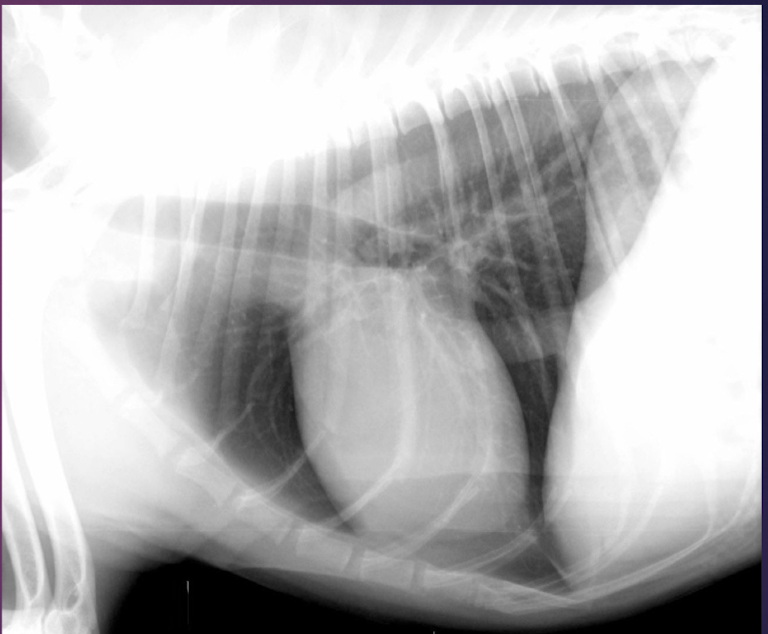

Right or left lateral?

Right